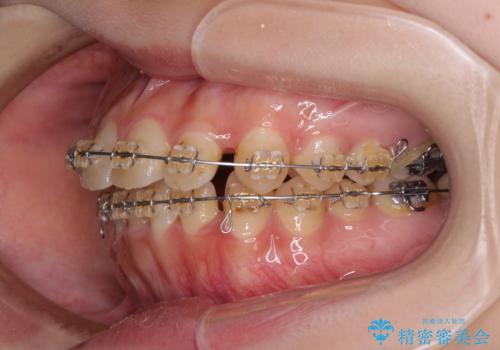

- 矯正装置

- 審美装置

- 大学病院にて装置を装着したものの、治療が十分に受けることができないとのことで転院をされた患者様です。

上顎歯列が前方にあり、口元が閉じにくくなっていたため、既に装着されている装置を使用して上顎歯列全体を後方に移動させていくこととしました。